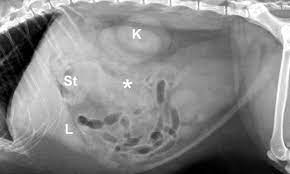

Primary pancreatic tumors are rare in dogs and cats. Despite medical advances, there is still just one way to determine whether or not your cat has inflammatory bowel disease or some type of cancer, and that is with a biopsy. Eating too much fatty food is a clear pancreatitis risk for dogs, notes the american kennel club, but the link between too much fat and pancreas problems in cats is still being studied. The symptoms of pancreatic cancer in cats can be realized only at the end of the disease process. The cat may develop muscle twitches and a lack of coordination.

Feline cancer initially manifests as a lump or bump on any parts of the body. The symptoms of pancreatic cancer tend to be vague and nonspecific, including weight loss, anorexia, hair loss in cats, vomiting, abdominal distension due to mass effect, depression. What are the symptoms pancreatic tumors in cats and dogs? Fever, jaundice, abdominal pain, digestion problems, weight loss, lethargy, weakness are all symptoms of pancreatic cancer in felines. Exocrine tumors include adenomas and adenocarcinomas, and endocrine tumors include insulinomas, gastrinomas, and glucagonomas. Tumors grow quietly, as your cat shows no symptoms. In most cats metastasis is found at the time of diagnosis, thus making treatment difficult for these patients. These tumors often lead to chronic inflammation of the pancreas called pancreatitis (which causes symptoms such as hunched back, repeated vomiting, diarrhea, poor appetite, dehydration, weakness and fever), or exocrine pancreatic insufficiency epi (which causes chronic diarrhea, weight loss and generalized poor health). Signs may include vomiting, depression, abdominal pain, loss of appetite, fever, diarrhea, and dehydration. When the pancreas becomes inflamed, the condition is called pancreatitis. It is caused by uncontrolled cell growth, and affects a wide range of cell types and organs in the body. Cancer in cats is the leading cause of death among cats. Summary of what is discussed in this article:

Pancreatitis Wild Rose Cat Clinic Of Calgary from www.catmd.ca Despite medical advances, there is still just one way to determine whether or not your cat has inflammatory bowel disease or some type of cancer, and that is with a biopsy. Both tumors are more common in dogs than cats. In some animals, a lump in the abdomen can be felt. Sometimes cats develop pancreatitis alongside inflammatory bowel disease or cholangiohepatitis (a liver disease), according to veterinary partner. How is the diagnosis made? In the vast majority of cases, symptoms only develop after pancreatic cancer has grown and begun to spread. Exocrine tumors include adenomas and adenocarcinomas, and endocrine tumors include insulinomas, gastrinomas, and glucagonomas. Fever, jaundice, abdominal pain, digestion problems, weight loss, lethargy, weakness are all symptoms of pancreatic cancer in felines.

If your cat appears to not have much of an appetite, yet still looks quite bloated when she stretches out, there could be a tumour present. Cats who develop fatty liver disease (hepatic lipidosis) at the same time can also show signs of jaundice like yellow gums and eyes, notes pet health network. These changes are usually more obvious in cases of acute pancreatitis. A pancreatic abscess is a collection of pus, usually near the pancreas. How is pancreatic cancer in cats diagnosed? When pancreatitis occurs in cats, it is often accompanied by inflammation of the liver and intestine. Externally we can see lumps and bumps. Symptoms of pancreatic cancer in cats pet owners may be able to catch the earliest symptoms of insulinomas if they pay close attention to their cat's behavior. It can occur in any breed or gender of cat. One of the first symptoms of pancreatic cancer is a loss of appetite, and this is a persistent symptom. If cats still will not eat, they may need to be fed with a large syringe. The symptoms of pancreatic cancer tend to be vague and nonspecific, including weight loss, anorexia, hair loss in cats, vomiting, abdominal distension due to mass effect, depression. Despite medical advances, there is still just one way to determine whether or not your cat has inflammatory bowel disease or some type of cancer, and that is with a biopsy.

Cats with a loss of appetite may respond better to moist food than to dry, because it is smellier. cats are motivated to eat by their sense of smell. What are the symptoms pancreatic tumors in cats and dogs? Some cats may show signs of jaundice because a pancreatic tumor can obstruct the flow of bile from the liver to the small intestine resulting in elevated levels of bile products in the blood causing the skin and mucous membranes to appear yellow. Pancreatic abscesses are a complication of pancreatitis. When the pancreas becomes inflamed, the condition is called pancreatitis.

Chronic Pancreatitis Cancer Therapy Advisor from www.cancertherapyadvisor.com The scarring also affects the insulin and digestive enzyme production thus leading to diseases like liver disease, (ibd) and diabetes. I did, however, have a dog with cancer and we really just followed her lead. Externally we can see lumps and bumps. The symptoms of pancreatic cancer are very similar to those of pancreatitis, and your veterinarian will likely perform tests to eliminate a diagnosis of pancreatitis if he suspects your cat may have pancreatic cancer. Pancreatic cancer symptoms in cats when a cat has pancreatic cancer, he will lose weight, vomit, have a belly that looks like it's stretched out, belly pain, will be jaundiced, he may be depressed and he won't want to eat much. Symptoms of pancreatic cancer in cats pet owners may be able to catch the earliest symptoms of insulinomas if they pay close attention to their cat's behavior. Because the insulin is released periodically, symptoms are not consistent and frequency of symptoms is not necessarily predictable. Both tumors are more common in dogs than cats.

Diagnosing & treating ibd vs cancer laurie goldstein, c.f.a. Some cats may show signs of jaundice because a pancreatic tumor can obstruct the flow of bile from the liver to the small intestine resulting in elevated levels of bile products in the blood causing the skin and mucous membranes to appear yellow. The symptoms of pancreatic cancer tend to be vague and nonspecific, including weight loss, anorexia, hair loss in cats, vomiting, abdominal distension due to mass effect, depression. In most cats metastasis is found at the time of diagnosis, thus making treatment difficult for these patients. Insulinomas are the most common type of pancreatic tumor, followed by adenocarcinomas. I have no experience caring for a cat with pancreatic cancer, or any kind of cancer. It is said to be complicated pancreatitis. Vomiting and abdominal pain can also be signs of the condition, but these signs are more common in people and dogs with pancreatitis than in cats. In order to allow the pancreas to rest and heal, oral foods will need to be stopped so iv therapy will need to be started. In some conditions, a mass can be felt in the dog's abdomen. Pet owners may be able to catch the earliest symptoms of insulinomas if they pay close attention to their cat's behavior. Feline cancer initially manifests as a lump or bump on any parts of the body. This is a medical condition when there is a collection of sterile pancreatic fluid enclosed by a tissue.